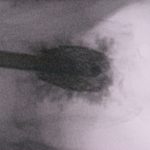

Η ενίσχυση του οστεοπορωτικού καταγματικού σπονδύλου και σπονδύλων, γίνεται ακόμη ασφαλέστερη όταν το Poly-Methyl-Metha-Crylate (ΡMMA) χορηγηθεί εντός εκπτυσσόμενου κλωβού από τιτάνιο, ο οποίος τοποθετείται με ειδική τεχνική εντός του σπονδυλικού σώματος. Το εγχεόμενο PMMA παραμένει εντός του κλωβού και κατ΄αυτό τον τρόπο περιορίζονται σημαντικότατα οι κίνδυνοι διαφυγής του PMMA ειδικά προς τον σπονδυλικό σωλήνα.

Εικόνα 3, α,β,γ: Αποκατάσταση των Οστεπορωτικών Σπονδυλικών Καταγμάτων με εκπτυσσόμενο κλωβό εκ τιτανίου προς τον σπονδυλικό σωλήνα.